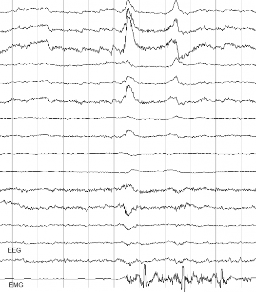

Combining two physiological signals EEG and EMG is one of the strong points for rehabilitation research. Where the first measures what is going on in the brain, the second measures what is going on in the muscles. Differences in activity in the EEG and in the EMG as compared to the normal pattern in healthy subject can point to the cause of the loss of motor functions.

EEG, TMS and EMG Response

Transcranial Magnetic Stimulation (TMS) is a technique that delivers a high energy magnetic pulse to the head of the patient which induces an electrical current in the brain tissue. When stimulating at for example the motor cortex the activation of the corresponding muscles can be monitored by measuring its EMG response. In order to investigate the effect of the TMS pulse in the brain, EEG can be measured simultaneously. (Rossi et al. 2004) The eego sports system provides a platform to combine such measurements in mobile settings without being bound to cables, power outlets or desktop computers to store the information.